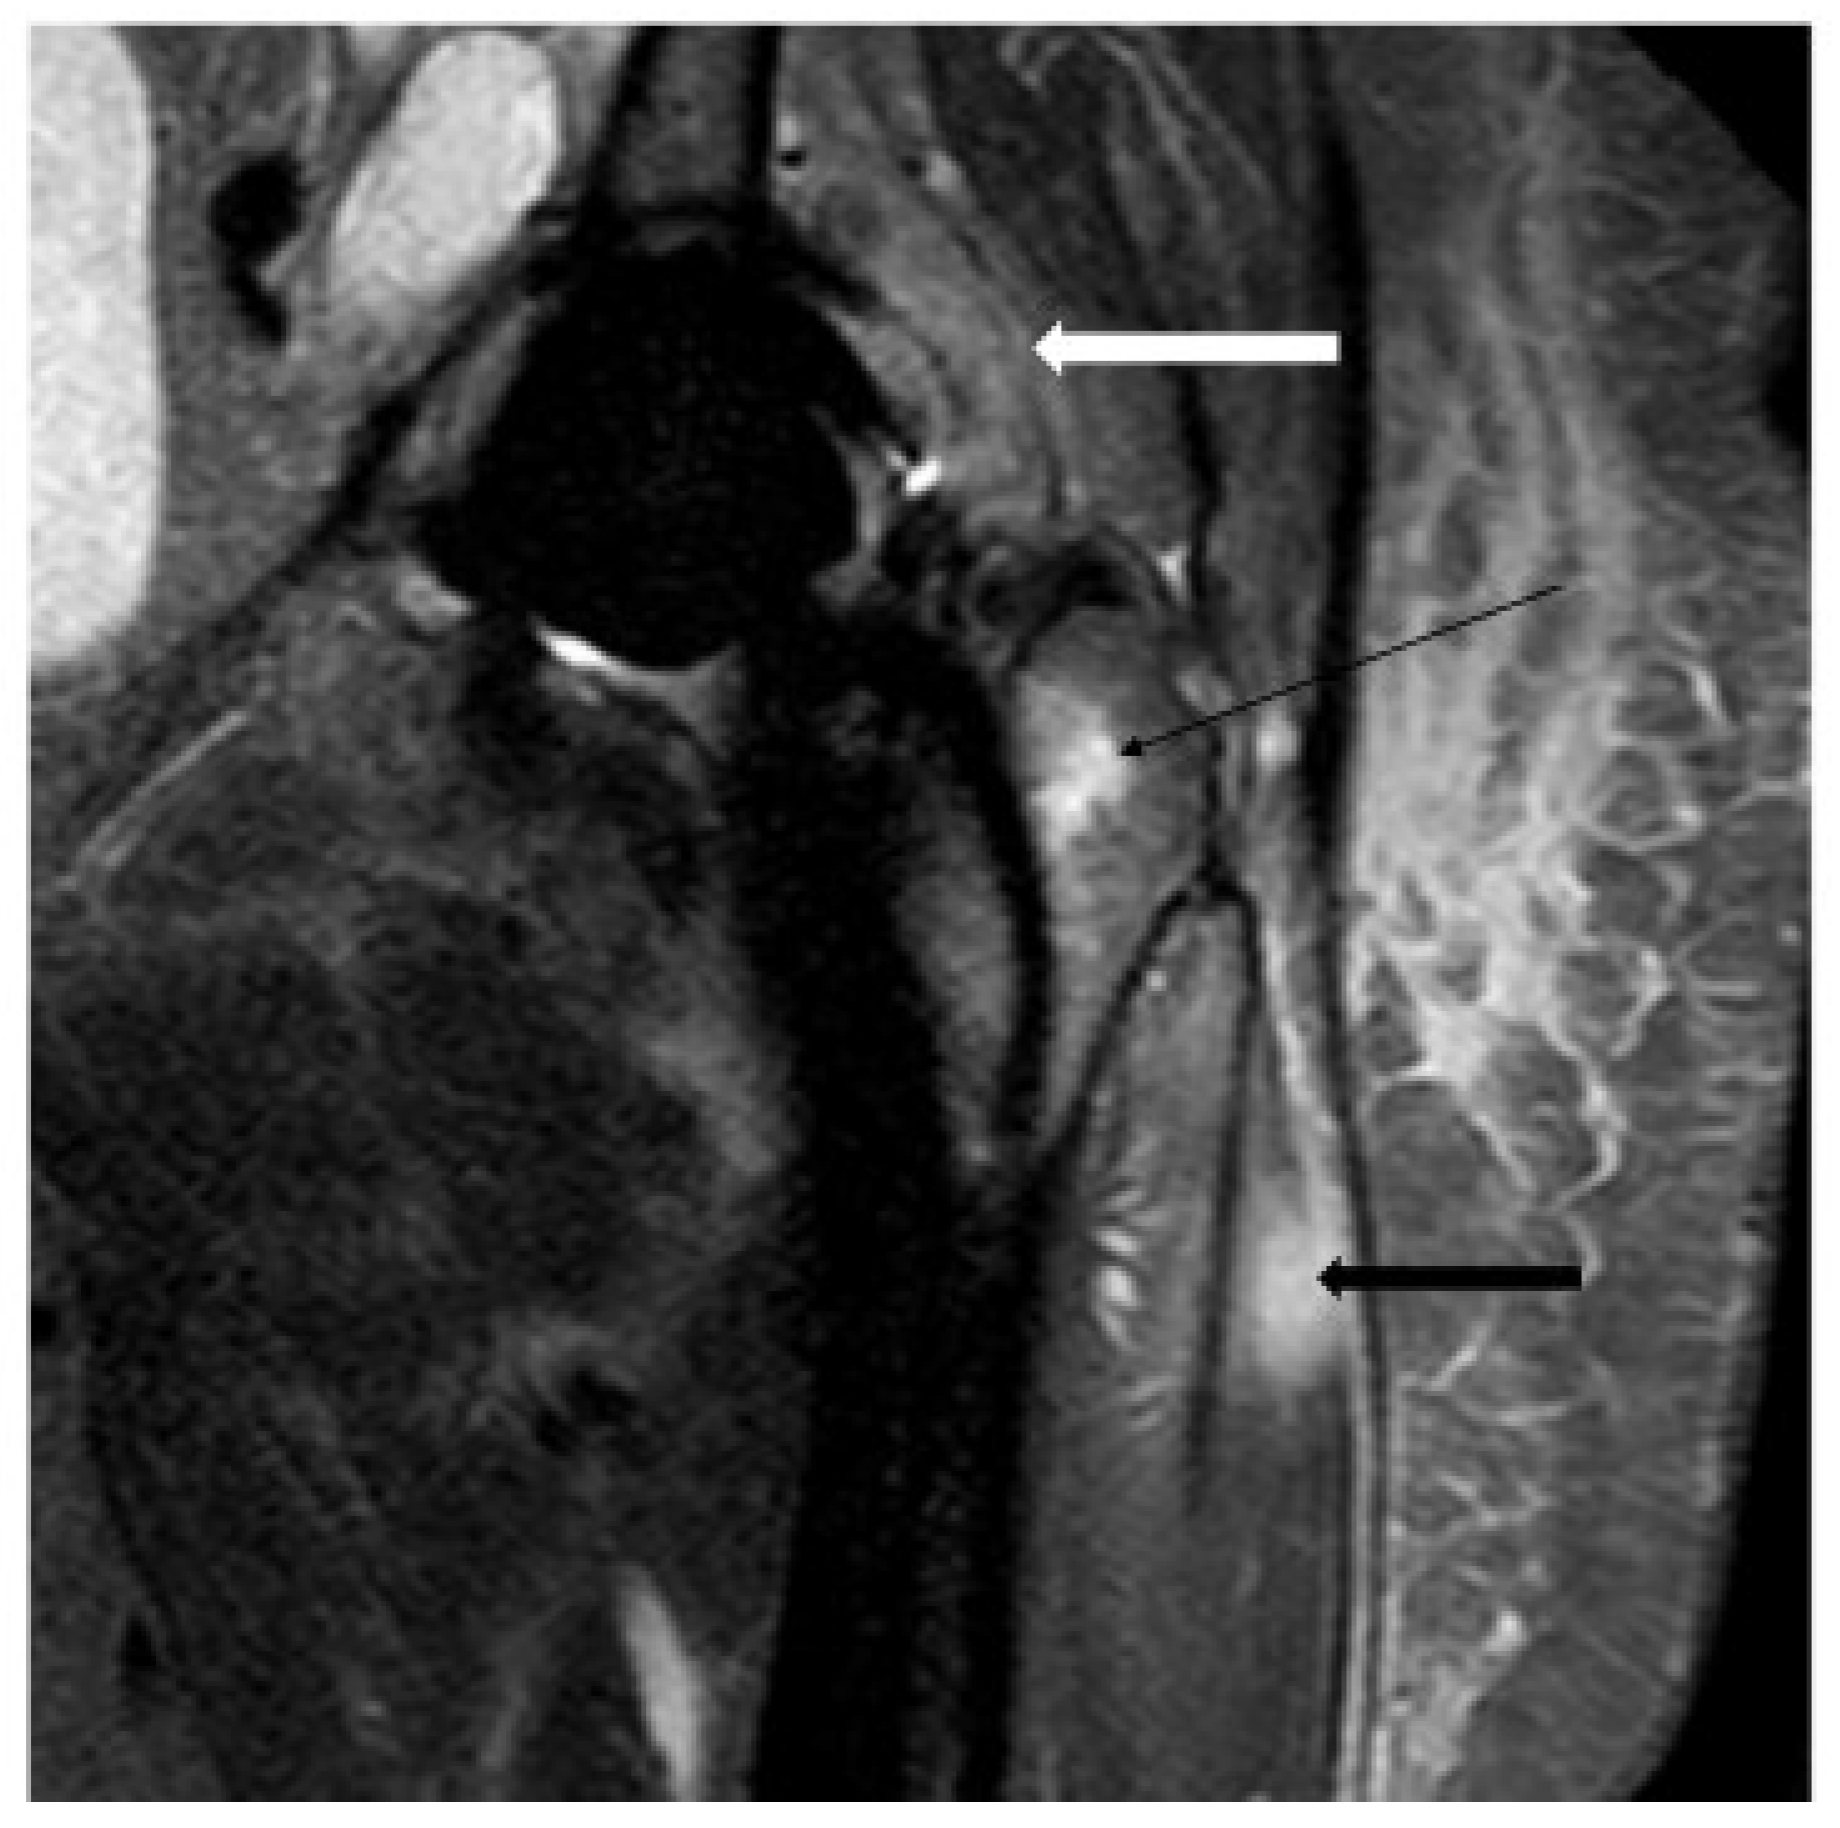

4.4. Magnetic Resonance Imaging